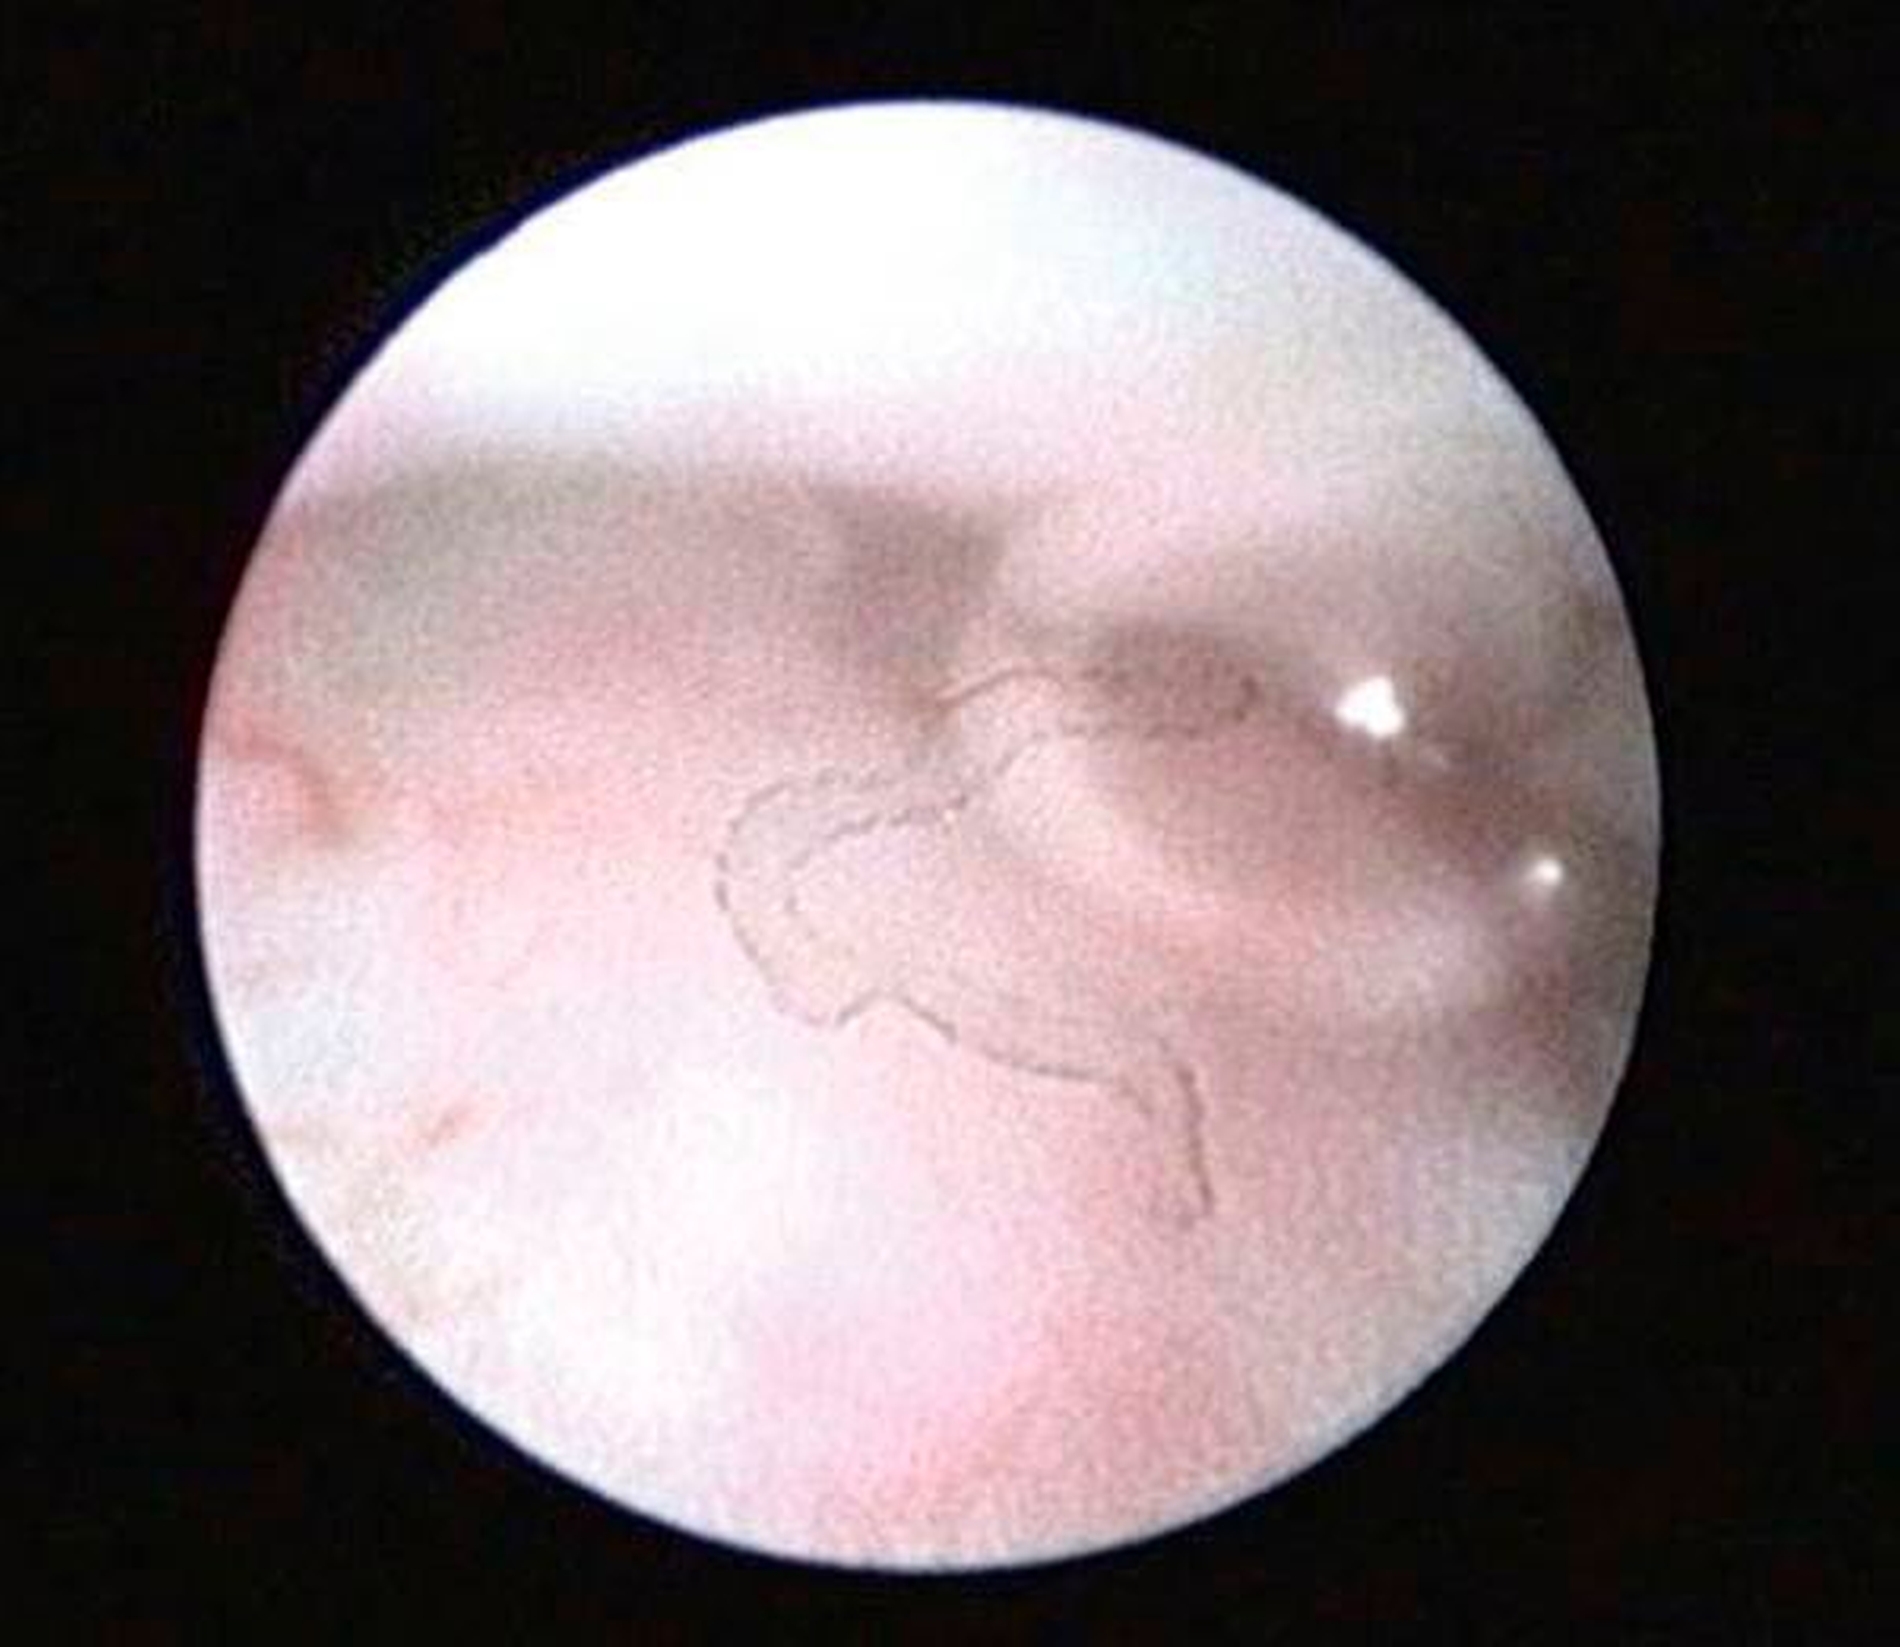

Die Kiefergelenksdestruktion wird als Ergebnis eines katabolen Prozesses verstanden, der die regenerativen Fähigkeiten des Gelenks überlagert und unter anderem durch eine kaskadenartige Aktivierung von Zytokinen vermittelt wird. Dabei kommt es neben einem Verstärkungseffekt durch die Synovial- und Gefäßproliferation zu einer Aktivierung von Osteoblasten. Zytokin-aktivierte Osteoblasten fördern die Rekrutierung und Aktivität von Osteoklasten, diese sezernieren wiederum Enzyme wie beispielsweise Matrix-Metalloproteasen (MMPs), die für den Abbau der extrazellulären Matrix (Hydroxylapatit und Kollagen) des Gelenks verantwortlich sind [Gunson et al., 2011; Zhang et al., 2016; Wang et al., 2012: Ge et al., 2011]. Die Schädigung des Gelenkknorpels wird dabei als „Chondromalazie“ bezeichnet und bei der arthroskopischen Diagnostik je nach Schweregrad im Stadium der Erweichung (Stadium 1), Furchung (Stadium 2), Fibrillation beziehungsweise Fransenbildung (Stadium 3) oder mit subchondraler Knochenexposition (Stadium 4) vorgefunden (Abbildungen 1 bis 3) [Quinn, 1989; Thomas et al., 1991].

Arthroskopisch existieren verschiedene Klassifikationen der Synoviitis, die im Wesentlichen das Ausmaß der beobachteten Gefäßproliferation und Hyperämie berücksichtigt (Abbildungen 4 bis 6) [Mc Cain et al., 1989; Gynther et al.,1994].

Selbst durch die MRT können bestimmte frühe Entzündungszustände der Kiefergelenke (beispielsweise die Synoviitis) bei fehlendem Gelenkerguss nicht direkt erfasst werden (radiologisch okkulte Kiefergelenksentzündungen). In der Praxis stellen symptomatische, aber radiologisch okkulte Entzündungszustände insbesondere im Fall einer Therapieresistenz auf konservative Therapiemaßnahmen (wie Schienen- und Physiotherapie) eine besondere Herausforderung dar, weil hier die Gefahr von Fehldiagnosen besonders groß ist (Abbildungen 4 bis 6).

Auch einige fortgeschrittene Gelenkveränderungen (beispielsweise die Synoviahypertrophie oder Diskusperforationen) sind durch die MRT direkt oft nicht nachweisbar [Liu et al., 2010; Zhang et al., 2009]. Diese Veränderungen lassen sich aber in der Regel durch die Arthroskopie nachweisen (siehe unten und Abbildung 6).

Die Kiefergelenksarthroskopie bietet bei gleichzeitiger Lavage eine überragende visuelle Diagnostik des oberen Gelenkraums (Abbildungen 1 bis 7, 13 und 14).

Zur Planung eines arthroskopischen Eingriffs am Kiefergelenk sollte ein möglichst aktuelles MRT der Kiefergelenke vorliegen, sofern hierfür keine Kontraindikationen bestehen. Dabei ist zu beachten, dass radioogisch diagnostizierte Pathologien durch die MRT nicht zwingend voraussetzend für eine Kiefergelenksarthroskopie sind. Bei Patienten mit symptomatischen Kiefergelenkschmerzen, aber radiologisch okkulten Kiefergelenksentzündungen ist die Kiefergelenksarthroskopie bislang immer noch das einzig relevante Verfahren zur Sicherung der Diagnose (Abbildungen 4 bis 6).